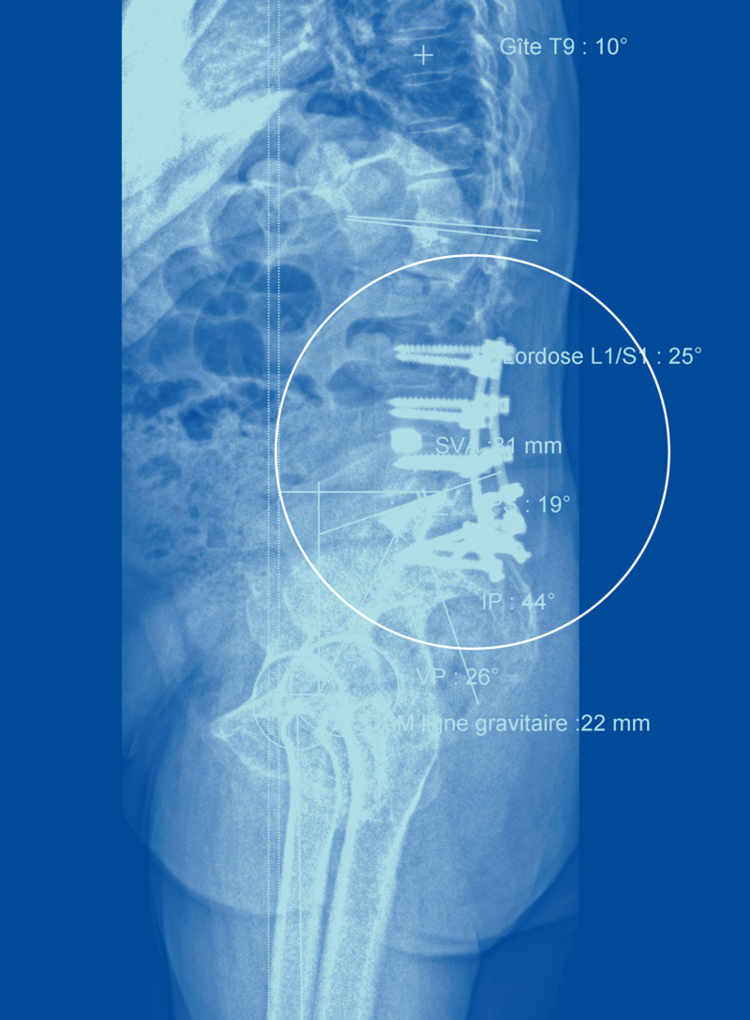

On a désormais identifié des paramètres normaux, poursuit le chirurgien, des angles (de cambrure par exemple) ou des mesures (l'emplacement du centre de gravité) qui permettent de prédire si une personne risque davantage de connaître des maux de dos. Telle patiente, par exemple, a un sacrum presque à l'horizontale, illustre le spécialiste: c'est très rare et cela cause naturellement une cambrure exagérée qui explique ses maux de dos.

Ces valeurs, l'EOS les calcule aisément et les fournit rapidement. Une fois munis de ces données, les spécialistes comprennent mieux l'origine des maux de dos. Ces mesures sont également précieuses pour déterminer où opérer pour être le plus efficace, de même que pour évaluer comment la colonne s'est repositionnée après une opération.